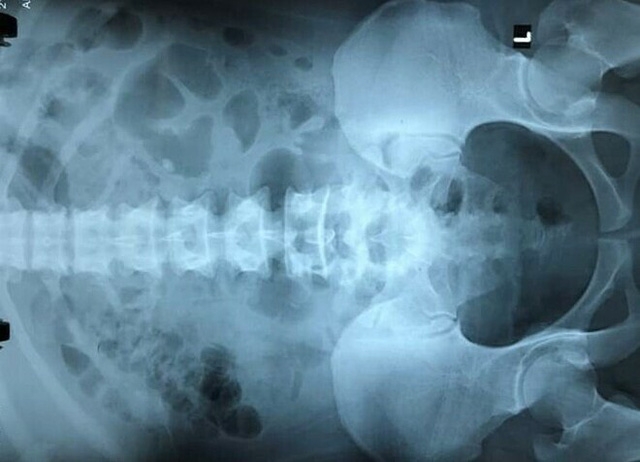

Các thói quen ăn uống tùy tiện như sử dụng nhiều thịt đỏ, đường, muối, uống ít nước, thiếu ngủ,...,được cho là nguyên nhân gây suy thận.